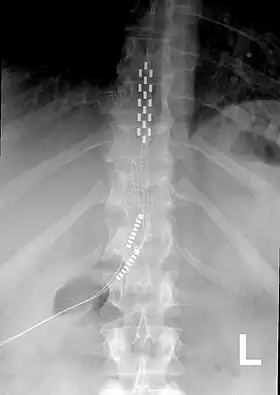

Neurostimulation for chronic pain is primarily through the use of spinal cord stimulators.[11] These devices deliver electrical stimulation to different areas of the spine based on where they are implanted. Since 2012, Medtronic has produced spinal cord stimulators with accelerometers that can predict the patient's position. The device can be programmed to give additional electrical stimulation if the patient is thought to be in a more painful position.[12]